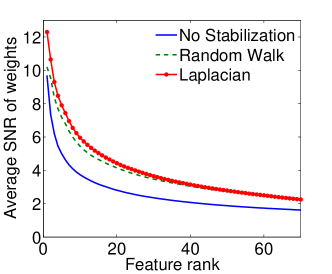

|

|

| (a) Cumulative, | (b) Stagewise (Shared), |

|

|

| (c) Stagewise (Separate), | (d) Stagewise (Separate), |

We now examine the models stability against data sampling and evaluate the stabilizing property of the proposed method (Sec. 6.2). For each fold, we generated samples, each of which was drawn randomly from % of training data. Each example resulted in a model, and the feature weights were recorded and finally the results of all folds – models – were combined. Figs. 5(a–d) show the indices (Eq. (5)) as functions of the rank list size , for all ordinal classifiers. The instability is clearly an issue – the average selected probability drops as more features are included. Using both the Laplacian and random walk regularization methods (Eqs. (9,10)), the improvement in stability is evidenced in all settings. The instability and stabilizing effect were similarly obtained with the indices (Figs. 6(a–d)).